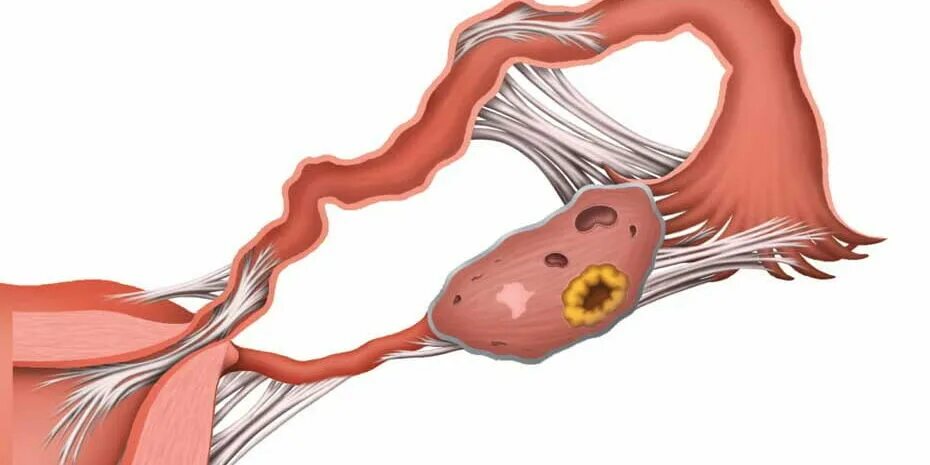

Аднексит диагностика